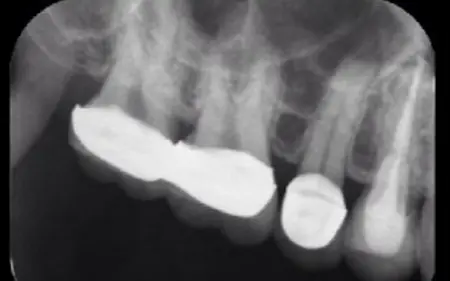

当院では、お口の中の健康とお口周りの美しさをトータル的に考えた治療を心がけています。歯科医院の目的は、虫歯・歯周病の歯の治療です。しかし最も力を入れるべきことは、虫歯や歯周病にならないための予防指導だと考えます。 プラークコントロールや歯の健康診断を定期的に受けることで大切な歯を守れるのです。丈夫で健康な歯は、何でも美味しく食べることができ、いつまでも若々しい口元と笑顔を保てます。当院の指導で、ご自分の歯で末永く健康にいきいきお過ごしいただきたいと思っています。